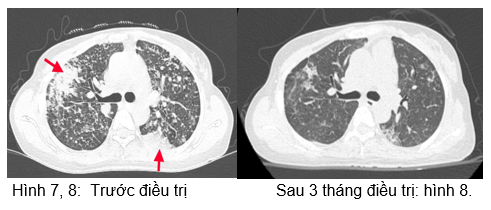

- Chụp cắt lớp vi tính lồng ngực:

Hình 9: Hình ảnh sau 6 tháng điều trị: Các đám đông đặc và kính mờ 2 phổi (giảm số lượng và kích thước sau các đợt điều trị).